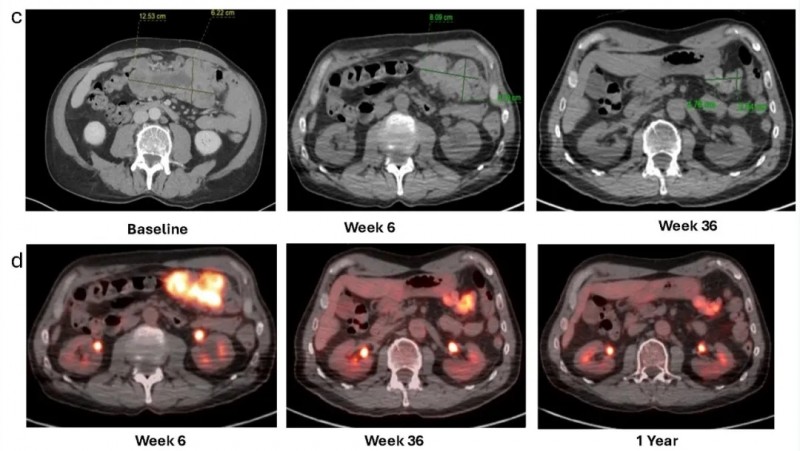

2025年11月17日,国际期刊《癌症免疫和免疫疗法》报道了一则振奋人心的案例:一名晚期黑色素瘤合并慢性淋巴细胞白血病/小淋巴细胞淋巴瘤(CLL/SLL)的患者,经肿瘤浸润淋巴细胞(TIL)治疗后,实现了放射学缓解与分子学完全缓解,为这类难治性患者的治疗提供了全新参考。

该患者为60余岁,2015年12月确诊下巴pT1a期皮肤黑色素瘤,经广泛切除术后随访至2021年2月,因颈部淋巴结肿大且细针穿刺活检(FNA)证实黑色素瘤复发,开启后续治疗。该患者先后经历了两次进展,并相继接受过帕博利珠单抗辅助治疗、伊匹木单抗+纳武利尤单抗、纳武利尤单抗联合替莫唑胺等治疗。后续考虑到患者无症状、CLL预后良好,且lifileucel已获FDA批准用于免疫检查点耐药性转移性黑色素瘤,最终决定采用lifileucel TIL方案治疗。

结果显示:根据实体瘤疗效评价标准(RECIST)v1.1,治疗6周后患者影像学表现达部分缓解(PR)。12个月随访时缓解持续,靶病灶缩小65%。PET/CT显示,治疗后6周~1年,代谢活性持续下降(详见下图c、d)。

▲图源“Front Immunol”,版权归原作者所有,如无意中侵犯了知识产权,请联系我们删除

在生化指标方面,血清乳酸脱氢酶(LDH,与肿瘤活性相关)在TIL输注后第7天达峰值842U/L(基线值290U/L),随后1个月内即恢复正常(169U/L),并在后续9个月随访中持续维持正常范围(详见下图e)。在分子标志物层面,循环肿瘤DNA(ctDNA,可精准反映肿瘤负荷)显示,基线平均肿瘤分子(MTM)值为1.28个/mL,TIL输注2周后ctDNA短暂升至8.38个/mL(推测为肿瘤细胞死亡释放所致),输注4个月后完全检测不到,12个月随访时仍保持完全分子学缓解(0MTM/mL,详见下图f)。